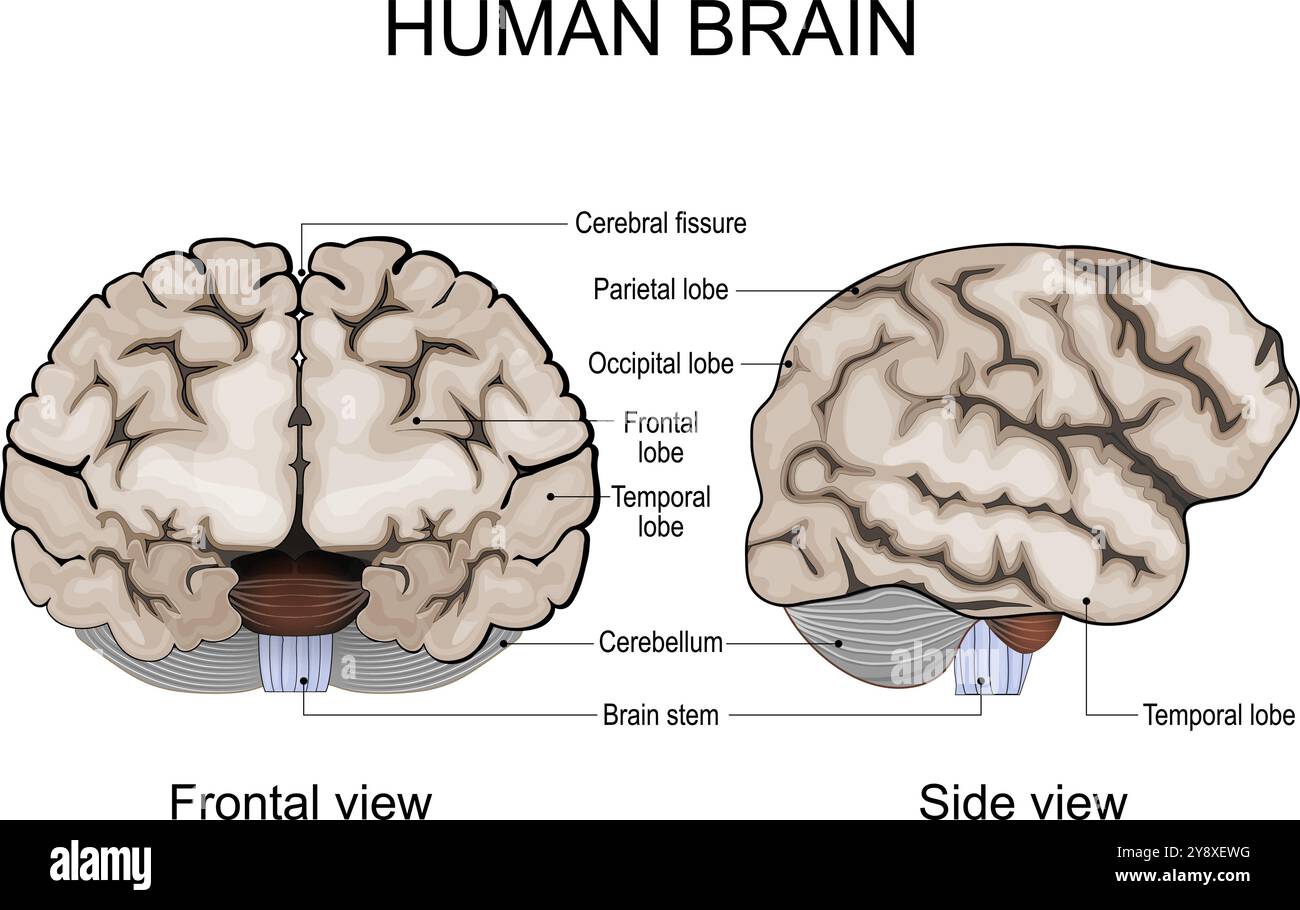

RF2R1KGAT–Struttura cerebrale umana. Emisferi e lobi della corteccia cerebrale. lobi frontali, temporali, occipitali e parietali. vista laterale e superiore

RF2Y8XEWG–Anatomia del cervello umano. Emisferi cerebrali, corteccia cerebrale, frontale, parietale, temporale, lobi occipitali, cervelletto e tronco cerebrale, fessura cerebrale.